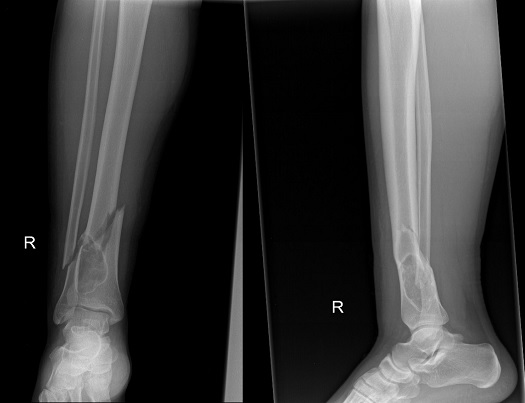

The patient was initially placed on a non-weight bearing protocol for eight weeks with only crutch and touch-toe ambulation. Follow-ups were carried out at two weeks, four weeks, eight weeks, sixteen weeks, eight months and one year post-operatively. At eight weeks, the ankle range of motion was regained and a healing callous started to form. The patient was, therefore, allowed to partially bear weight. At 4 months post-operatively, full weight bearing was started when the patient had a painless full range of ankle motion and x-rays revealed good incorporation of the allograft (Figure 6). Examination at eight months and 1 year post-operatively revealed full ankle strength and range of motion restoration with a complete filling of the defect and total fracture healing (Figure 7).

Figure 6 AP and lateral x-rays 4 months post-operatively-maintained osteosynthesis and good incorporation of the allograft within the lesion.

Figure 7 AP and lateral x-rays 1 year post-operatively. Complete resolution of the fracture.